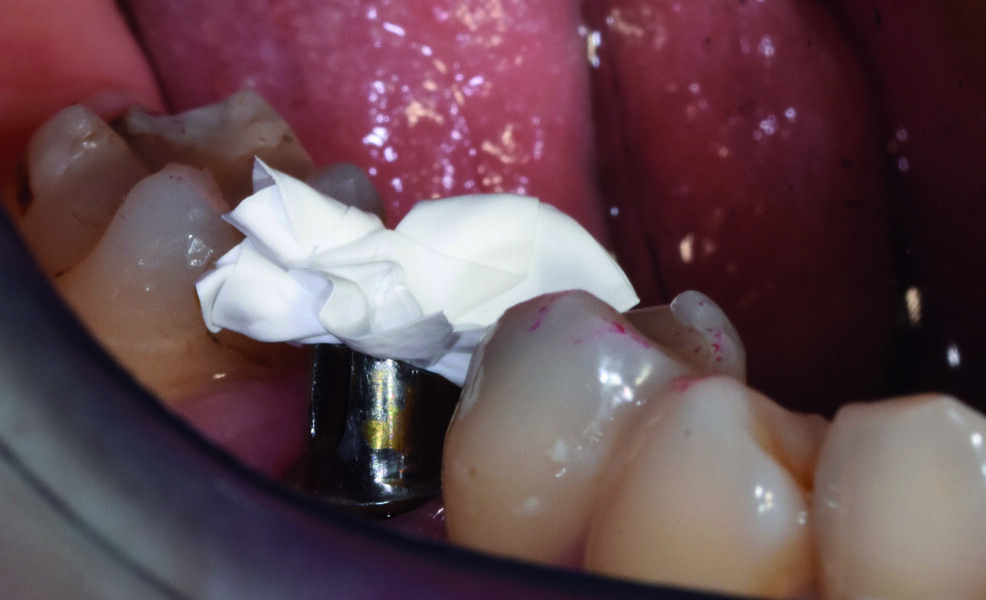

Dépose de la vis de cicatrisation remplacée par le transfert d’empreinte (Figs. 16 et 17). Prise d’empreinte à l’aide d’un transfert à ciel fermé, silicone en double mélange avec un porte-empreinte du commerce.

Fig. 16 : Mise en place du transfert d’implant à ciel fermé.